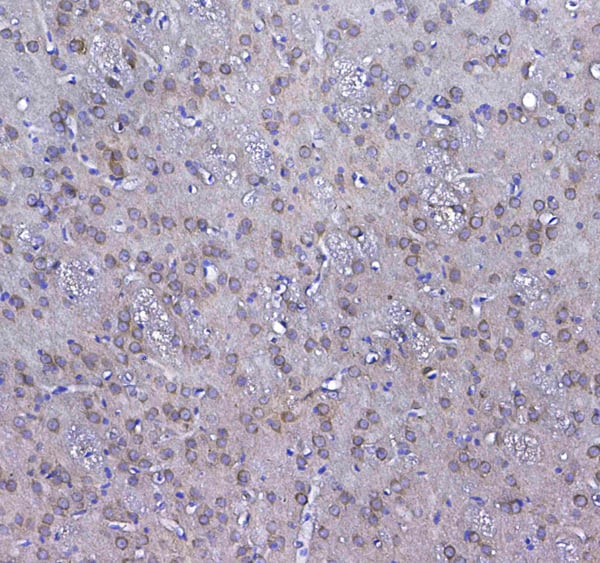

Cytoglobin, Polyclonal Antibody (Cat# AAA11681)